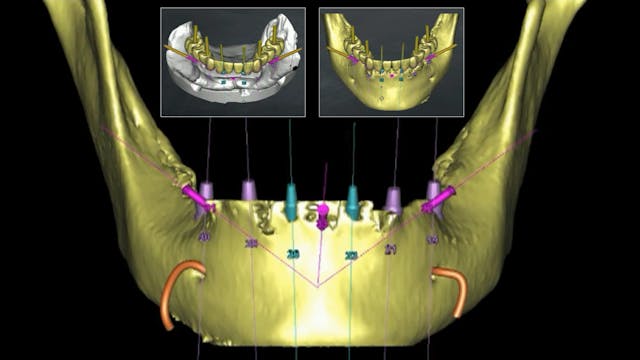

In this dental video by Dr Jovanovic a meticulous procedure involving the uncovering of two anterior implants with a mucogingival technique employing a roll flap and a vestibuloplasty with a gingival strip graft sourced from the palate. Through step-by-step demonstrations, the video showcases the precision and expertise required for successful implant uncovering and soft tissue management.

Furthermore, the video highlights the integration of cutting-edge digital technology in dental practice by illustrating the immediate temporization phase. Oral scanning and 3D printing are utilized to create custom temporaries, ensuring optimal fit and aesthetics for the patient during the crucial soft tissue healing period.